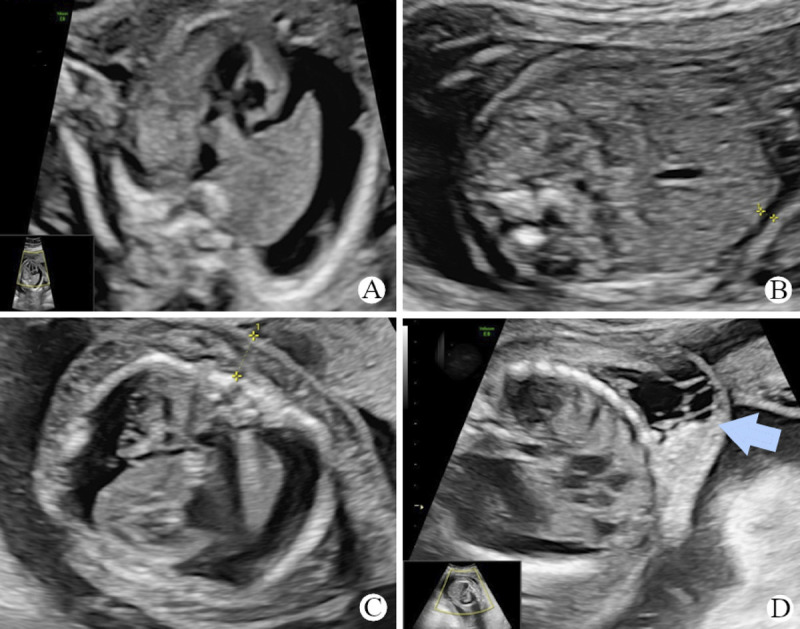

胎儿水肿可由免疫或非免疫原因引起。免疫原因通常包括红细胞异体免疫,而非免疫原因包括结构畸形、非整倍体、感染、淋巴系统疾病、遗传综合征等。在一个罕见而复杂的病例中,我们遇到了胎儿水肿的表现,其特征是混合表型,表明遗传和潜在的免疫病因。母亲,恒河阴性,有不良产科事件史。在21周时,目前的胎儿被诊断为水肿。母体血液测试显示恒河猴同种异体免疫,间接库姆斯试验呈阳性,稀释比例为1:512,存在抗d、抗c和抗e抗体。胎儿血样显示o型阳性血型,血红蛋白水平为10克/分升。尽管对胎儿进行了宫内输血,但没有任何改善;相反,胎儿水肿恶化,并伴有颈部和腋窝肿块的出现。胎儿DNA的外显子组测序显示胎儿是SERPINA11基因致病性变异的纯合子,而PIEZO1基因致病性变异的复合杂合子。此外,SERPINA11和PIEZO1基因的致病变异组合在胎儿水肿病例中尚未被描述。由于同时存在免疫性和非免疫性水肿,该病例在管理方面提出了重大挑战。我们描述了在这个病例的临床管理中所面临的一些诊断挑战。

Fetal hydrops can stem from immune or nonimmune causes. Immune causes often involve red cell alloimmunization, whereas nonimmune causes encompass structural malformations, aneuploidy, infections, lymphatic system disorders, genetic syndromes, and more. In a rare and complex case, we encountered a fetal hydrops presentation characterized by blended phenotypes, indicating both a genetic and an underlying immune etiology. The mother, Rhesus negative, presented with a history of adverse obstetric events. At 21 weeks, the current fetus was diagnosed with hydrops. Maternal blood tests unveiled Rhesus alloimmunization, featuring a positive indirect Coombs test at a 1:512 dilution and the presence of anti-D, anti-C, and anti-E antibodies. Fetal blood sampling revealed an O-positive blood group with a hemoglobin level of 10 gm/dL. Despite administering intrauterine transfusion to the fetus, there was no improvement; instead, the fetal hydrops worsened, accompanied by the emergence of nuchal and axillary masses. Exome sequencing of fetal DNA revealed the fetus was homozygous for a pathogenic variant in the SERPINA11 gene and compound heterozygous for a pathogenic variant in the PIEZO1 gene. Furthermore, the combination of pathogenic variants in SERPINA11 and PIEZO1 genes has not been described in cases of fetal hydrops before. This case posed significant challenges in management due to the concurrent presence of both immune and nonimmune hydrops. We describe some of the diagnostic challenges faced in clinical management of this case.